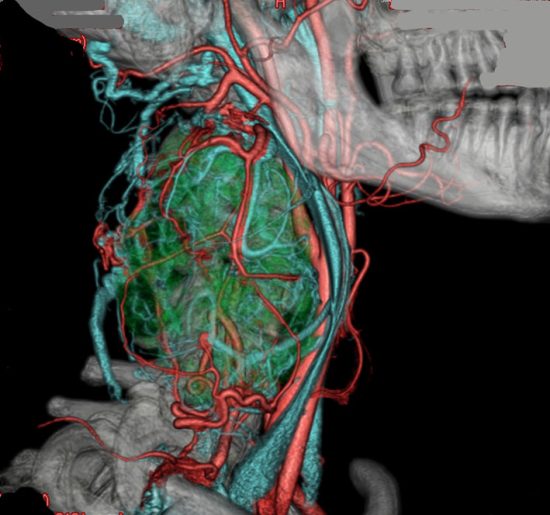

10歳くらいから頸部に腫瘍があり生検術をされましたが診断がつかず,31歳までなにも治療をしなかった患者さんです。20年間でかなりゆっくり大きくなりました。

30代で,血行性肺転移が多発しているという診断を受けました。20年以上の病歴があり,多くの血管に富むhypervascular tumorであったために,良性腫瘍であるパラガングリオーマの肺転移という術前診断で頸部腫瘍の摘出をしました。

全摘出して術後経過に問題はありませんでしたが,病理診断は,全体がリンパ球と胚中心様の構造でCastleman diseaseでした。発熱や倦怠感などの症状がなく軽症の単中心性キャッスルマン病として経過したものかもしれません。